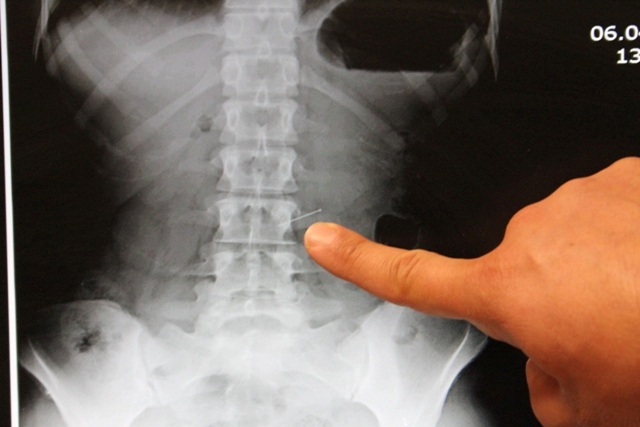

Ameliyatı gerçekleştiren Genel Ceraahi Uzmanı Op. Dr. Bülent Erenoğlu, iğnenin 3 saat süren başarılı bir operasyonla mideden çıkarıldığını söyledi.

Bu tür vakalarda, hastaneye vakit kaybetmeden gelinmesi gerektiğini ifade eden Erenoğlu,"Endoskopi yöntemi ile iğneyi başarılı bir şekilde çıkarttık. Tabi midenin dolu olması, midenin çalışması anlamına geliyor. Dolayısıyla iğne midede bir kaç yeri zedelemiş. Fakat şu anda hastamızın bir sıkıntısı yok. Gözlem amaçlı yatırdık. Taburcu etmeyi düşünüyoruz." dedi.